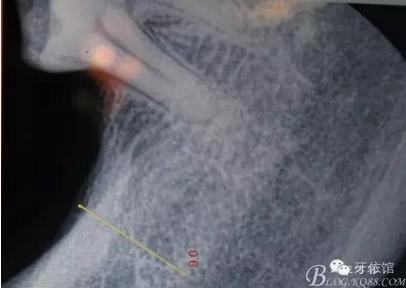

患者女,45歲,右上6于多年前牙髓失活后充填,未作冠,術前不久,進食時不幸劈裂。檢查發(fā)現(xiàn):右上6充填物脫落,近遠中向縱劈,x光見根管內(nèi)無充填物。同時有右上7、右下7缺失。計劃:右上6,7,右下7種植修復。右上6為即可種植,同時做內(nèi)提。

X光片

術后x光片,右上6直接上愈合基臺,但未完全就位,右下7手術過程略

這是術后1月的片子,重新就位愈合基臺